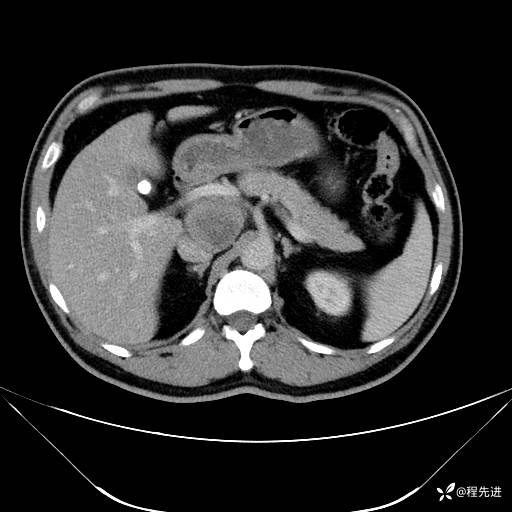

【腹盆】特别精彩病例|发现腹膜后肿物1月余

主诉:发现腹膜后肿物1月余

现病史:患者1月余前查体,行超声检查提示:后腹膜囊实性肿块;慢性胆囊炎伴胆囊内结石;无腹痛腹胀,不伴腹泻发热等;偶感腰背部酸痛。

CT平扫+增强: